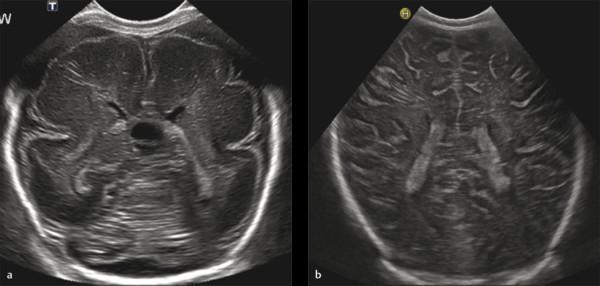

PEDİATRİK TRANSFONTANEL ULTRASON (BEYİN ULTRASONU)

Transfontanel ultrason yeni doğan bebeklerde sıklıkla kullanılmakla birlikte bebeklerin kafa kemikleri kapanana kadar (yaklaşık 6-9 ay) yapılabilir. Bu inceleme ile kafa kemiklerinin henüz kapanmayan alanları pencere olarak kullanılarak beyin yapıları, damarlar, beyin omurilik sıvısı ve beyin zarları değerlendirilir. Yeni doğan bebeklerde özellikle prematürite olması durumunda beyin gelişiminin normal olup olmadığı değerlendirilir.

Prematür bebeklerde beyin içi kanama olasılığı daha yüksektir. Bu durumda da ultrason inceleme olası kanamanı yeri, büyüklüğü, çevre dokulara basısı gibi konularda fikir verir. Yine beyin omurilik sıvısının (BOS) artış gösterdiği durumlarda bu artışın derecelendirilmesi ve tedavinin planlanması için en uygun görüntüleme yöntemidir. Beyin içerisinden doğumsal olarak gelişen kitleleri değerlendirmek için de öncelikle ultrason inceleme kullanılır.